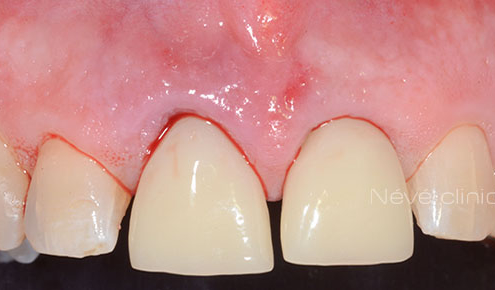

- Les implants dentaires peuvent être placés sans avoir à soulever votre gencive.

- Dans certains cas, une prothèse provisoire implanto-portée peut être fabriquée avant même que les implants dentaires ne soient posés.